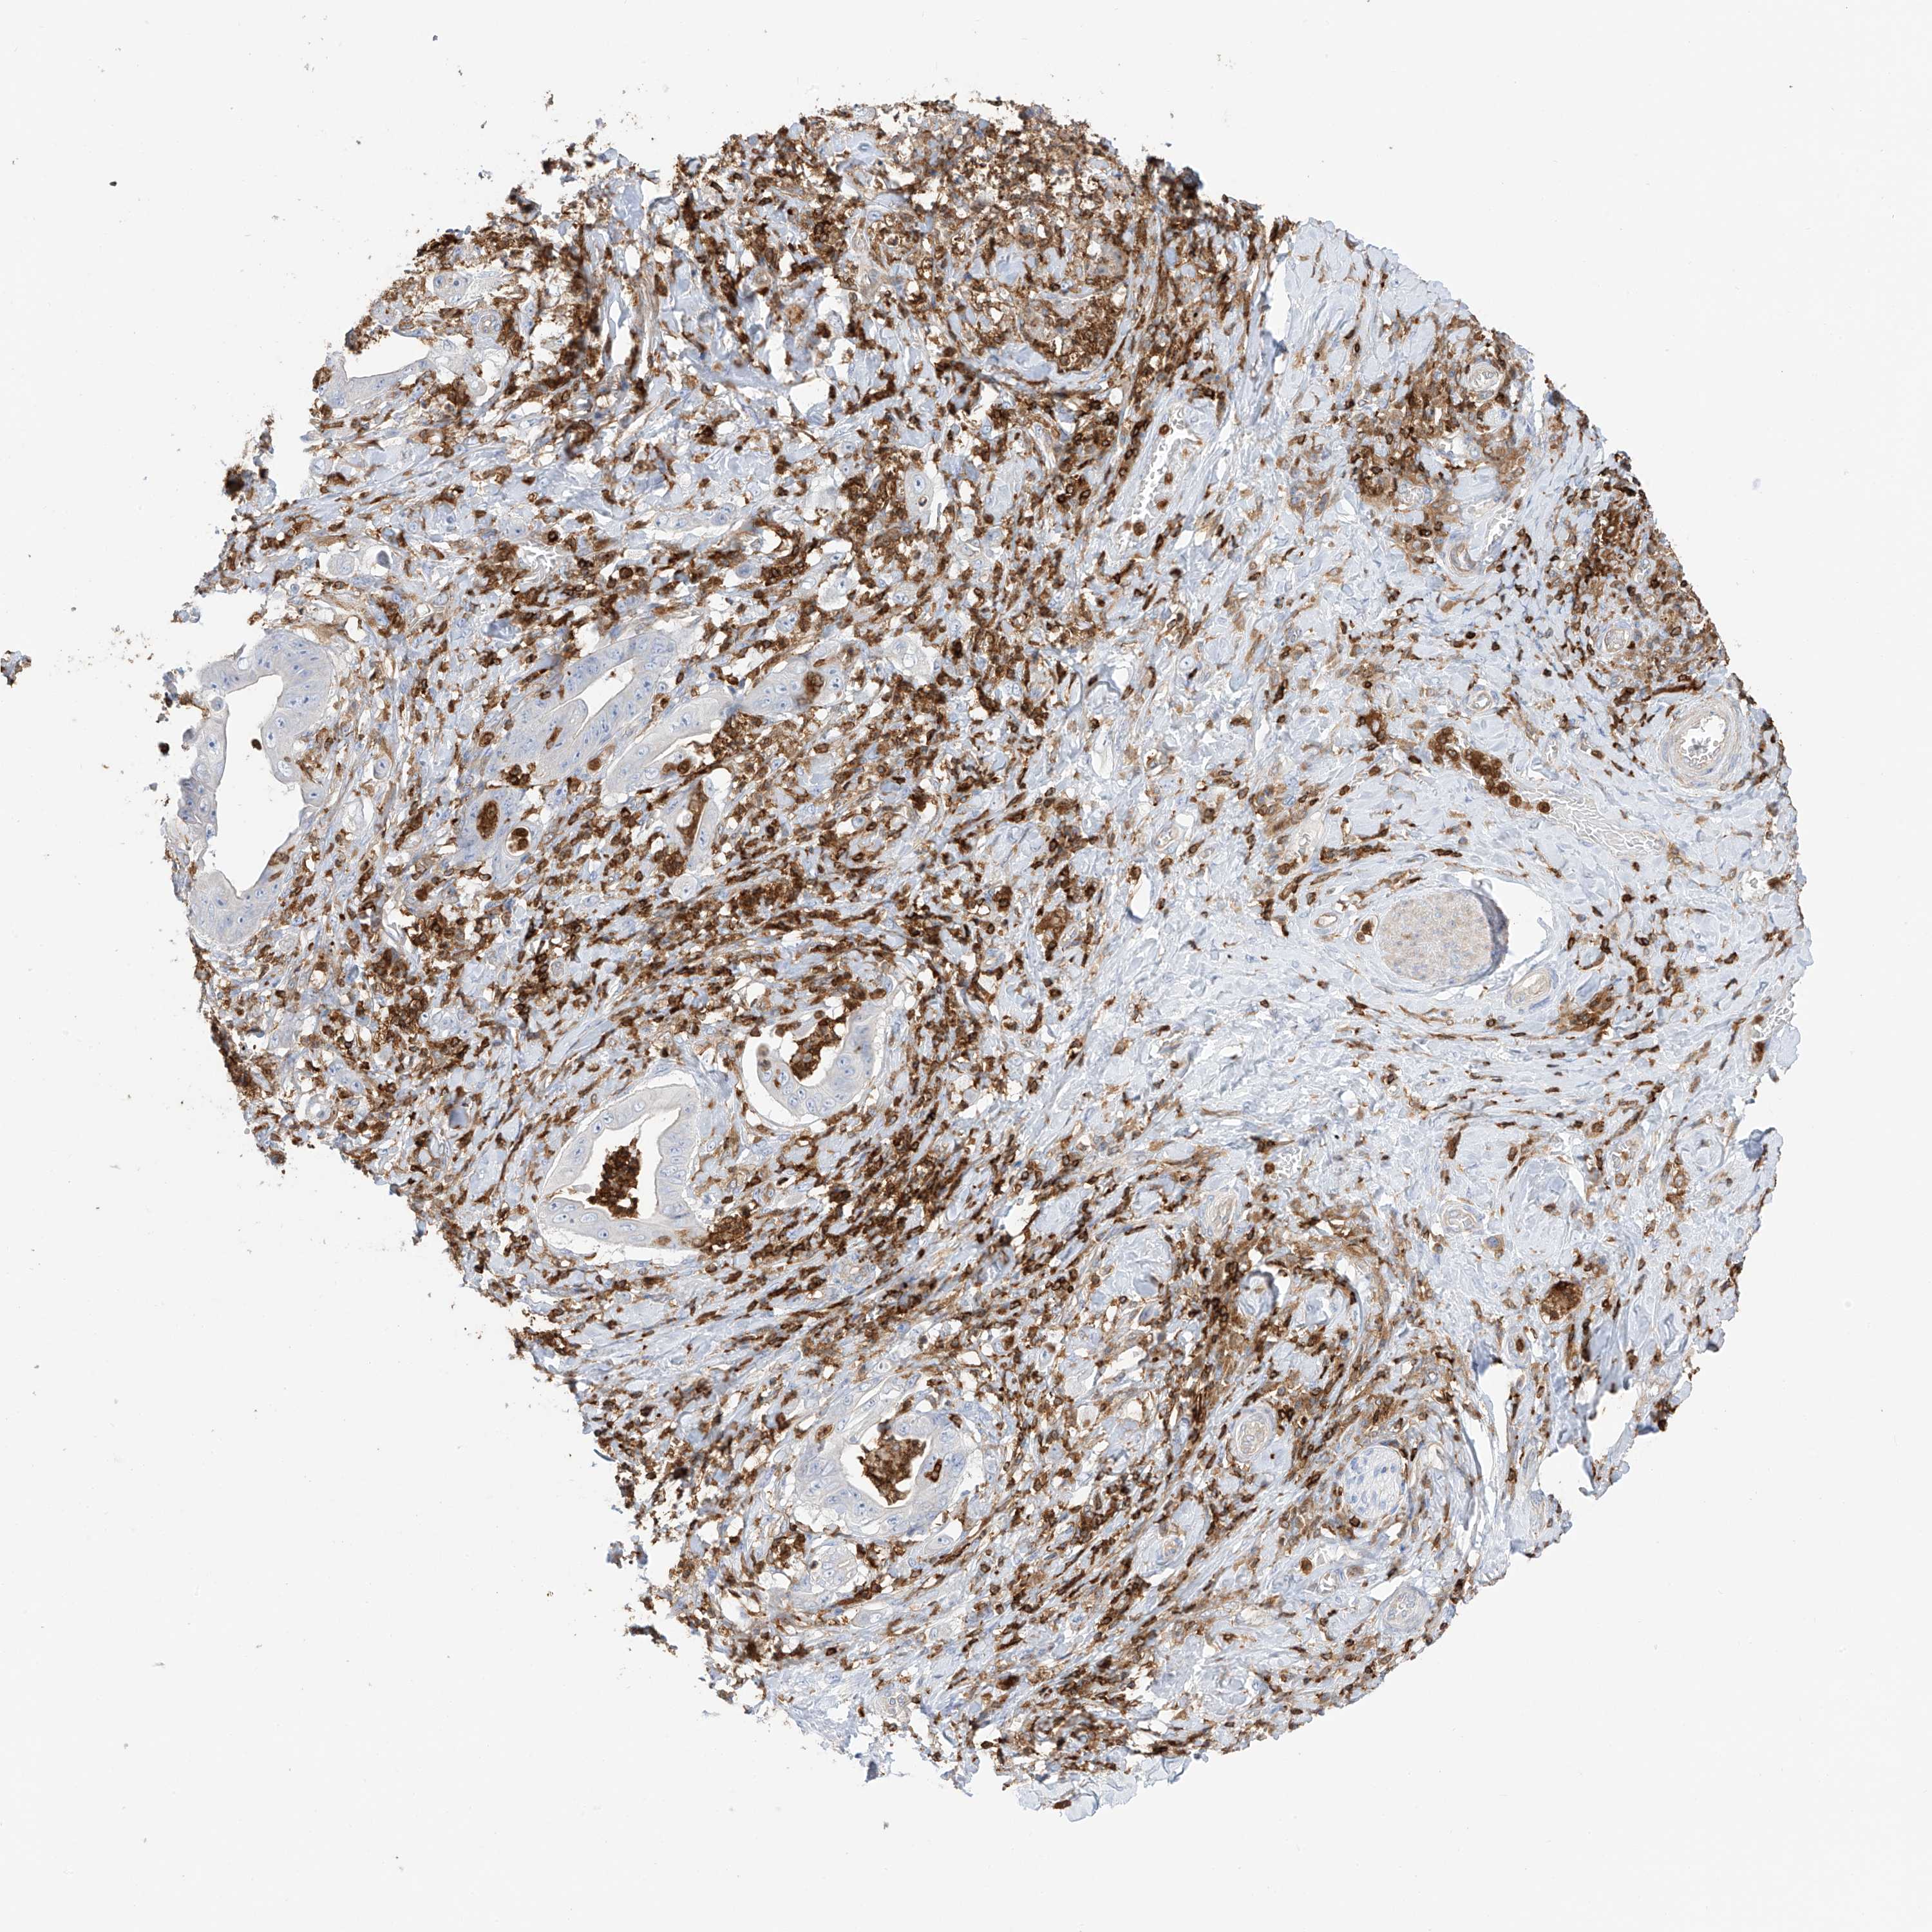

STOMACH CANCER - Protein expressioni

A mouse-over function shows sample information and annotation data. Click on an image to view it in a full screen mode. Samples can be filtered based on level of antibody staining by selecting one or several of the following categories: high, medium, low and not detected. The assay and annotation is described here.

Note that samples used for immunohistochemistry by the Human Protein Atlas do not correspond to samples in the TCGA dataset.

Antibody stainingi

Antibody staining in the annotated cell types in the current human tissue is reported as not detected, low, medium, or high, based on conventional immunohistochemistry profiling in selected tissues. This score is based on the combination of the staining intensity and fraction of stained cells.

Each image is clickable and will lead to virtual microscopy that enables deeper exploration of all samples and also displays staining intensity scores, fraction scores and subcellular localization as well as patient and tissue information for each sample.

Antibody HPA061395

Adenocarcinoma, NOS